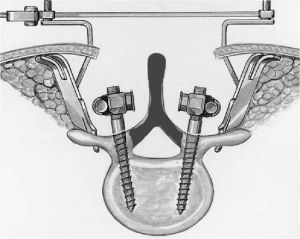

Вследствие того, что наиболее частой причиной стеноза позвоночного канала является нестабильность в позвоночнике, операцию декомпрессии позвоночного канала необходимо дополнять транспедикулярной фиксацией позвоночника. (Рис.6а,б).

Кроме того, выполнение ламинэктомии всегда должно заканчиваться транспедикулярной фиксацией в соответствии с рекомендациями зарубежных исследователей. В противном случае у пациента обычно развивается нестабильность, что приводит к болям в поясничном отделе позвоночника. Транспедикулярная фиксация при выполнении декомпрессии из мини доступа проводится чрескожно, т.е. через разрезы длиной около 2см.